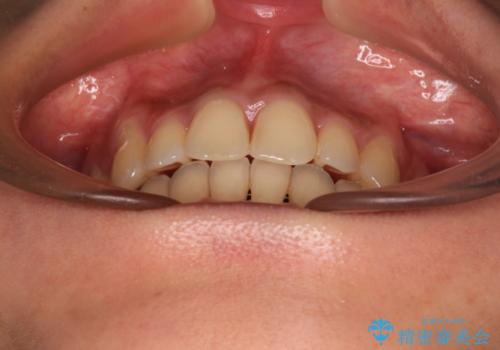

- 八重歯と上下前歯のでこぼこを気にして来院された患者様です。

上下前歯部叢生のスペース獲得のため、上下顎左右小臼歯各1歯(計4本)を抜歯して、ワイヤー装置にて矯正治療を行うこととしました。

上下の正中位置が大きくずれていたため、上下正中が合わないまま終了することが予想されましたが、思っていた以上にスムーズに歯が移動し、満足いただける仕上がりとなりました。